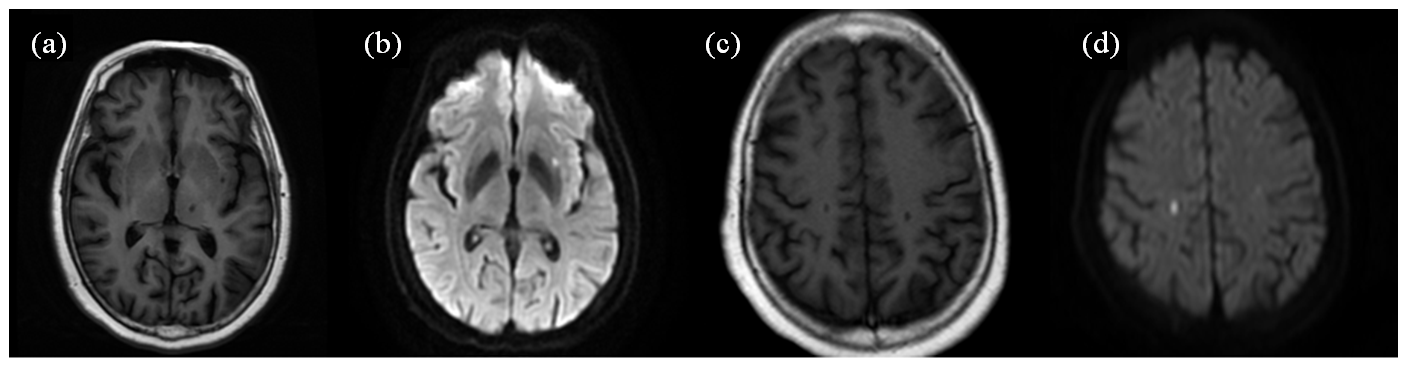

| 图2 一位单发急性脑梗塞复发患者磁共振轴位SE T1WI (a、c)、DWI (b、d)图像. 患者首次住院,行磁共振检查显示,左侧外囊单发腔梗呈长T1信号(a),DWI弥散受限呈高信号(b);患者康复出院后4个月出现临床症状,行磁共振检查显示,右侧顶叶单发腔梗灶,呈长T1信号(c),DWI扩散受限呈高信号(d) |

| Fig. 2 Magnetic resonance axial SE T1WI (Fig. a, c) and DWI (Fig. b, d) of a patient with recurrent single lesion of acute stroke.The patient was admitted to the hospital for the first time, and an MRI showed a single lumen infarction in the left external capsule with a long T1 signal (Fig. a) and diffusion-limited DWI with a high signal (Fig. b). The patient developed clinical symptoms four months after discharge from rehabilitation, an MRI showed a single lumen infarction in the right parietal lobe with a long T1 signal (Fig. c) and diffusion-limited DWI with a high signal (Fig. d) |